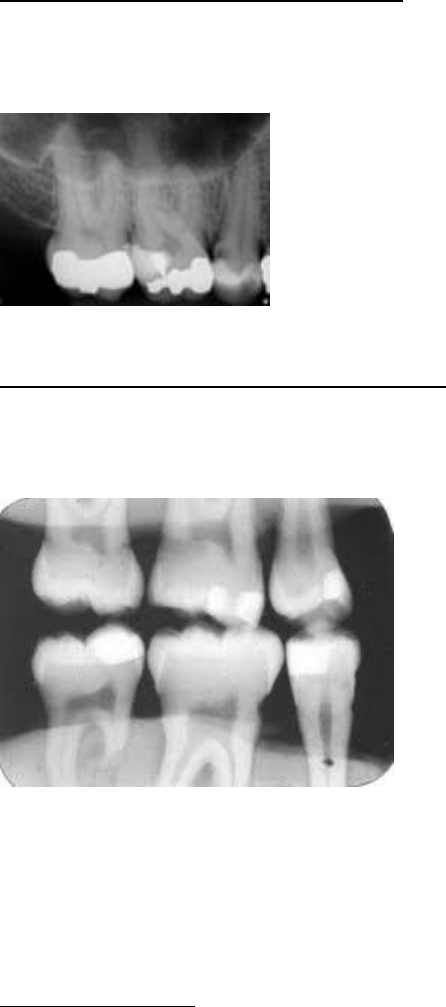

imagem sugestiva de imagem radiopaca em dente 17 (O), 16 (MO)

Imagem sugestiva de material protético em coroa 46, imagem sugestiva de material obturador satisfatório de 46,

imagem sugestiva de lesão periapical 46, resina de baixa radiopacidade em 47

Imagem sugestiva de material obturador aquém do limite apical em 15, imagem sugestiva de reconstrução coronária

protética 15, imagem sugestiva de restaurador insatisfatório (OD) em 14 , imagem sugestiva de pino intra radicular

em 14